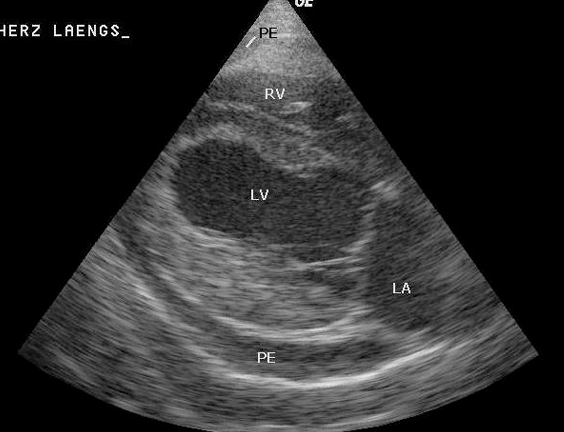

확진

심장과 심낭 사이에 Echo-free space

(딱 봐도 쪼그라들어 보임)

echo가 dense한 pericardium